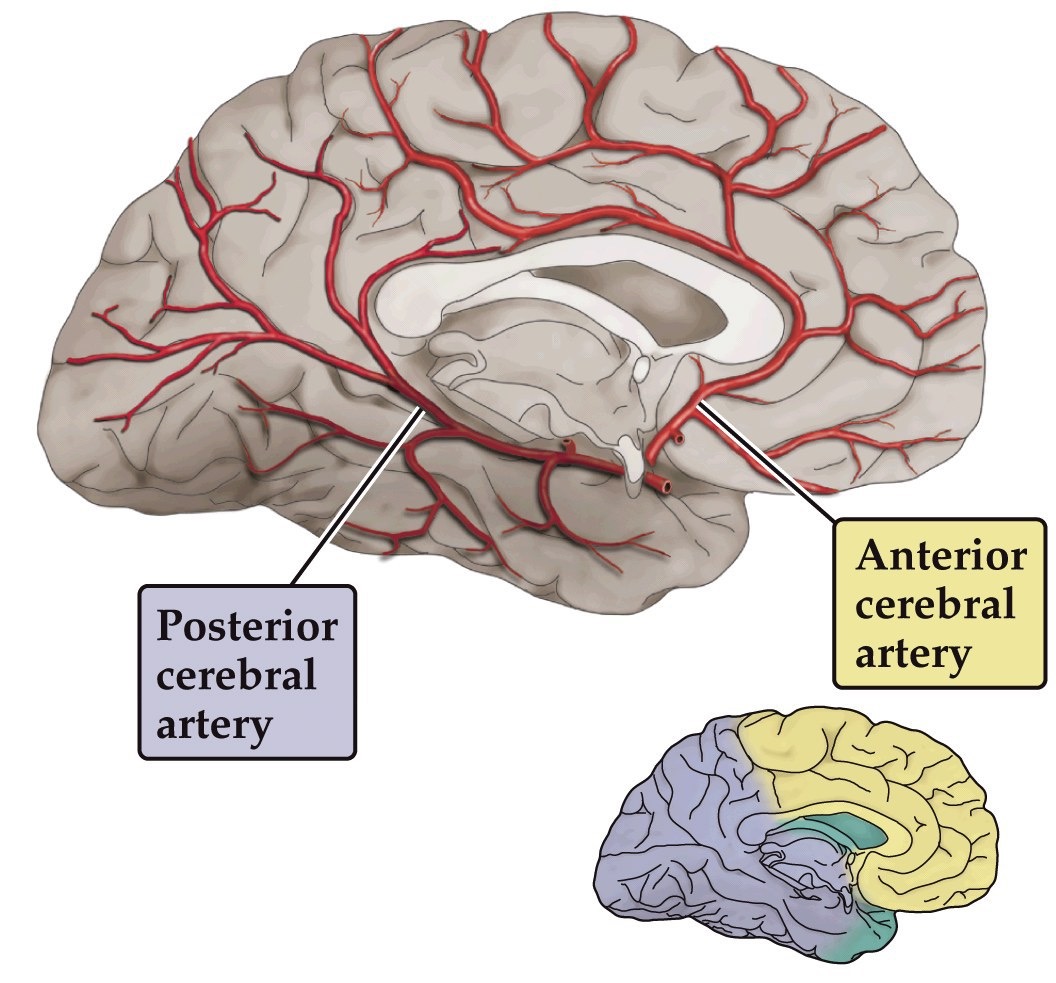

Cerebral circulation